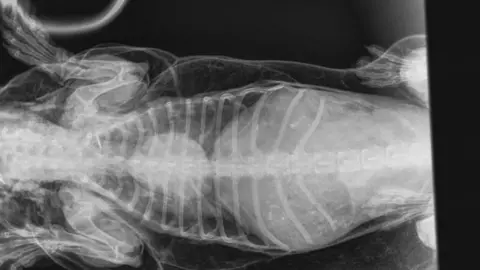

X-rays showed every time the pet drew a breath, air was being forced under its skin and was affecting its heart.

Tests were carried out and the dog was diagnosed with sub-cutaneous emphysema, an abnormal collection of air under the skin.

"There were no external injuries that would explain how air had got under the skin, so we suspected that an internal injury to the airway could have been allowing the air in.

"Every time he took a breath, some of the inhaled air escaped through a hole in his windpipe."